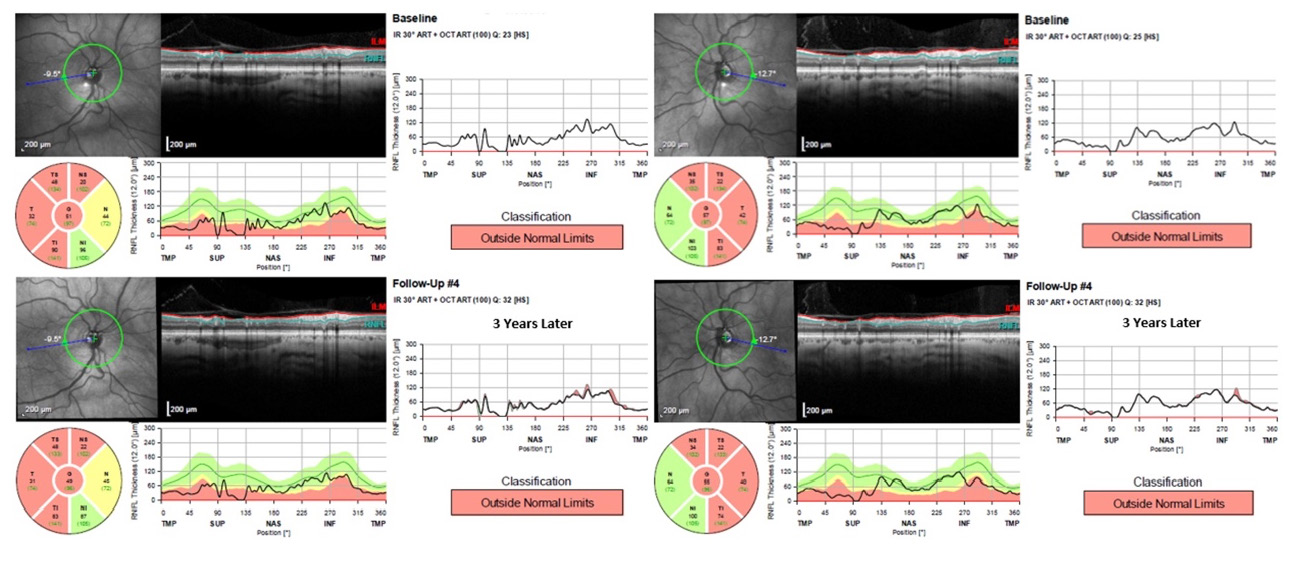

Historically, the retina has been unremarkable with no signs of diabetic retinopathy in either eye. No disc hemes were noted at this exam, and see Image 4 for past fundus photos. See Image 5 for recent OCT testing of the RNFL with baseline data from three years prior. See Image 6 for a summary of three years of HVF testing.

Image 5. Baseline RNFL OCT and a 3-year follow-up of the right (a) and left (b) eye of Patient 2. Click to enlarge

Given the characteristics of the superior disc in SSONH, it is understandable that multiple studies have confirmed thinning of the superior retinal nerve fiber layer (RNFL) as measured by optical coherence tomography (OCT).9 Interestingly, further studies have found that the inferotemporal sector is spared in patients with SSONH while the remaining RNFL is thinned when compared to the normal population.9,13 Recognizing this characteristic is another helpful tool in differentiating SSONH from glaucoma as glaucoma frequently impacts the inferotemporal sector.

Case 2: The RNFL is significantly reduced superiorly in both eyes. The thinning also affects all sectors except for the inferonasal sector. Contrary to some studies, thinning is also present in the inferotemporal region. This raises suspicion for concomitant glaucoma, especially given their ocular hypertension. (Image 4)